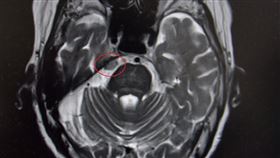

牙痛治不好要注意!可能是腦瘤作祟?

29歲的年輕媽媽艾瑪(Emma Webster)某日...